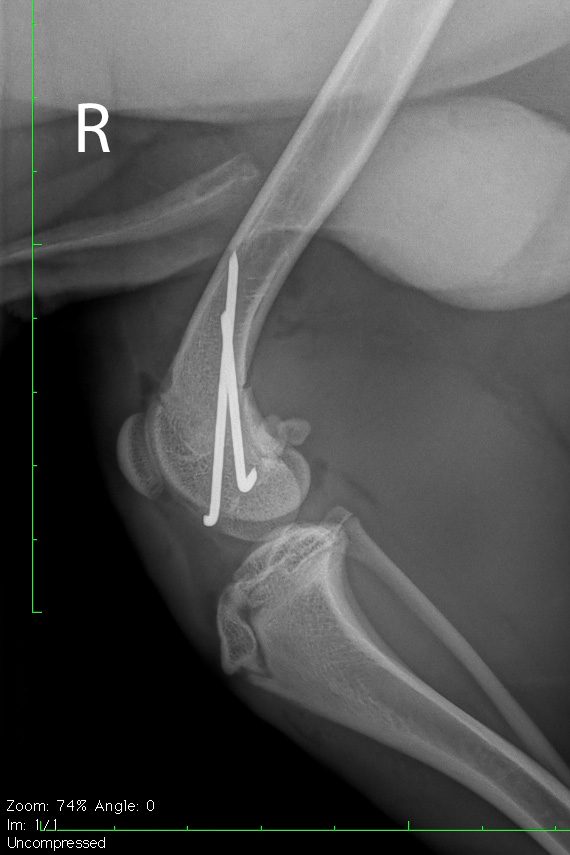

Salter Harris Fraktur post-operativ

Kontrollröngtenaufnahme in der 2. Ebene.